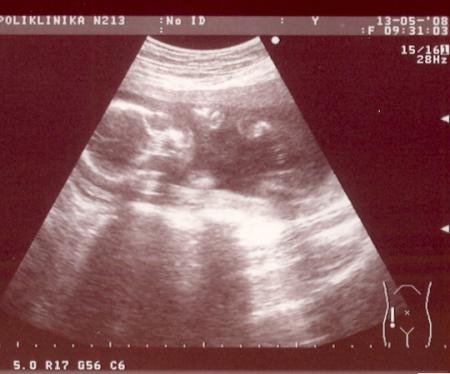

УЗИ - НАМ 20НЕДЕЛЬ

Прямая речьБыли сегодня на УЗИ - НАМ 20НЕДЕЛЬ.Так долго ждали этого срока чтобы нам сказали кто у нас мальчик/девочка - ведь мальчик уже есть, а врач так не уверенно, мол похоже на девочку.Может она специалист фиговый - ведь срок нормальный.